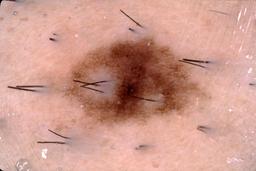

{

"age_approx": 40,

"anatom_site_general": "lower extremity",

"concomitant_biopsy": true,

"dermoscopic_type": "contact non-polarized",

"diagnosis_1": "Benign",

"diagnosis_2": "Benign melanocytic proliferations",

"diagnosis_3": "Nevus",

"diagnosis_4": "Nevus, Congenital",

"diagnosis_confirm_type": "histopathology",

"image_type": "dermoscopic",

"lesion_id": "IL_2066173",

"melanocytic": true,

"patient_id": "IP_2256945",

"sex": "female"